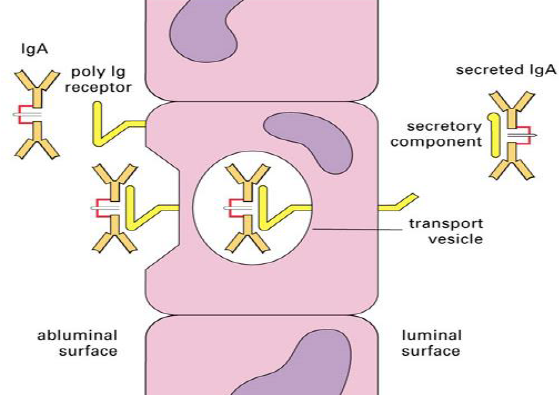

IgA

- Dimer (20% of IgA in human)

- J chain 串聯

- Compoment 黏在上面

- IgA 會去有黏液的腔室, Complement 能保護

- IgA 會去有黏液的腔室, Complement 能保護

- 在哪?

- IgA1: 鼻腔、淚水、唾液與母乳

- IgE: Colon

S IgA

- 初乳, 母乳, 口水

- Secretory component (SC) 由黏膜上皮製造